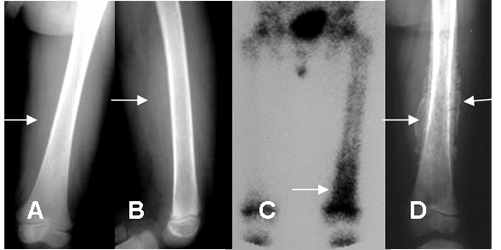

Fig 29. Osteomielitis aguda.

A: Rx AP y B: Rx lateral. Aumento de la densidad en los tejidos blandos del fémur distal, por edema de tejidos blandos. No se detectan alteraciones óseas.

C: Gamagrafía. Depósito anormal del trazador en el fémur distal, por osteomielitis aguda.

D: Rx AP. Después de 20 días de evolución se aprecia reacción perióstica, que corresponde a involucro.